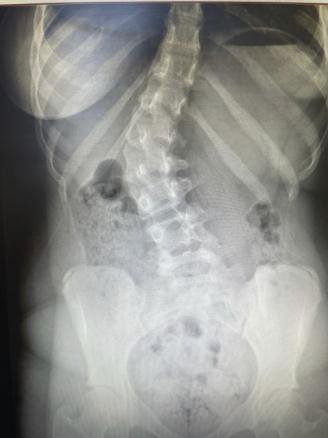

Un bilan radiographique confirme le diagnostic de scoliose, avec un angle de Cobb mesuré à 31° (fig. 1 et 2 ).

Un bilan radiographique du rachis entier debout, de face et de profil est nécessaire. Il permet de mesurer l’angle formé par la tangente de la vertèbre supérieure et de la vertèbre inférieure les plus inclinées (angle de Cobb), ainsi que le stade d’ossification de la crête iliaque, témoin de l’avancée de la croissance (stade de Risser). L’utilisation du système de radiographie EOS, moins irradiant, est à privilégier lorsqu’une surveillance régulière est indiquée.